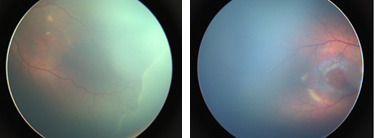

The target is to develop a deep neural network that correctly classifies input color fundus photograph (CFP) as ROP positive or ROP negative (Fig 1). In the transfer learning framework, the feature space is a space of 3D tensors, the feature distribution is the distribution of CFPs taken from infants, and the label space consists of ROP positive and ROP negative.